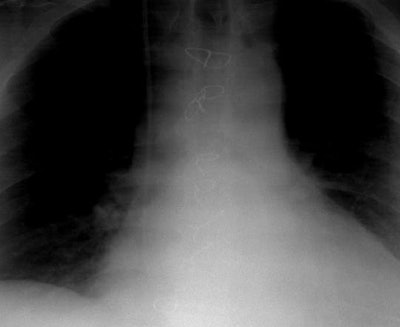

Mediastinitis:

The two coned views below compare the position of the sternal wires at discharge (following median sternotomy), and when the patient presented with fevers 3 weeks later- at which time there had been migration of a sternal wire- an indicator of mediastinitis.

Sternal wire migration: